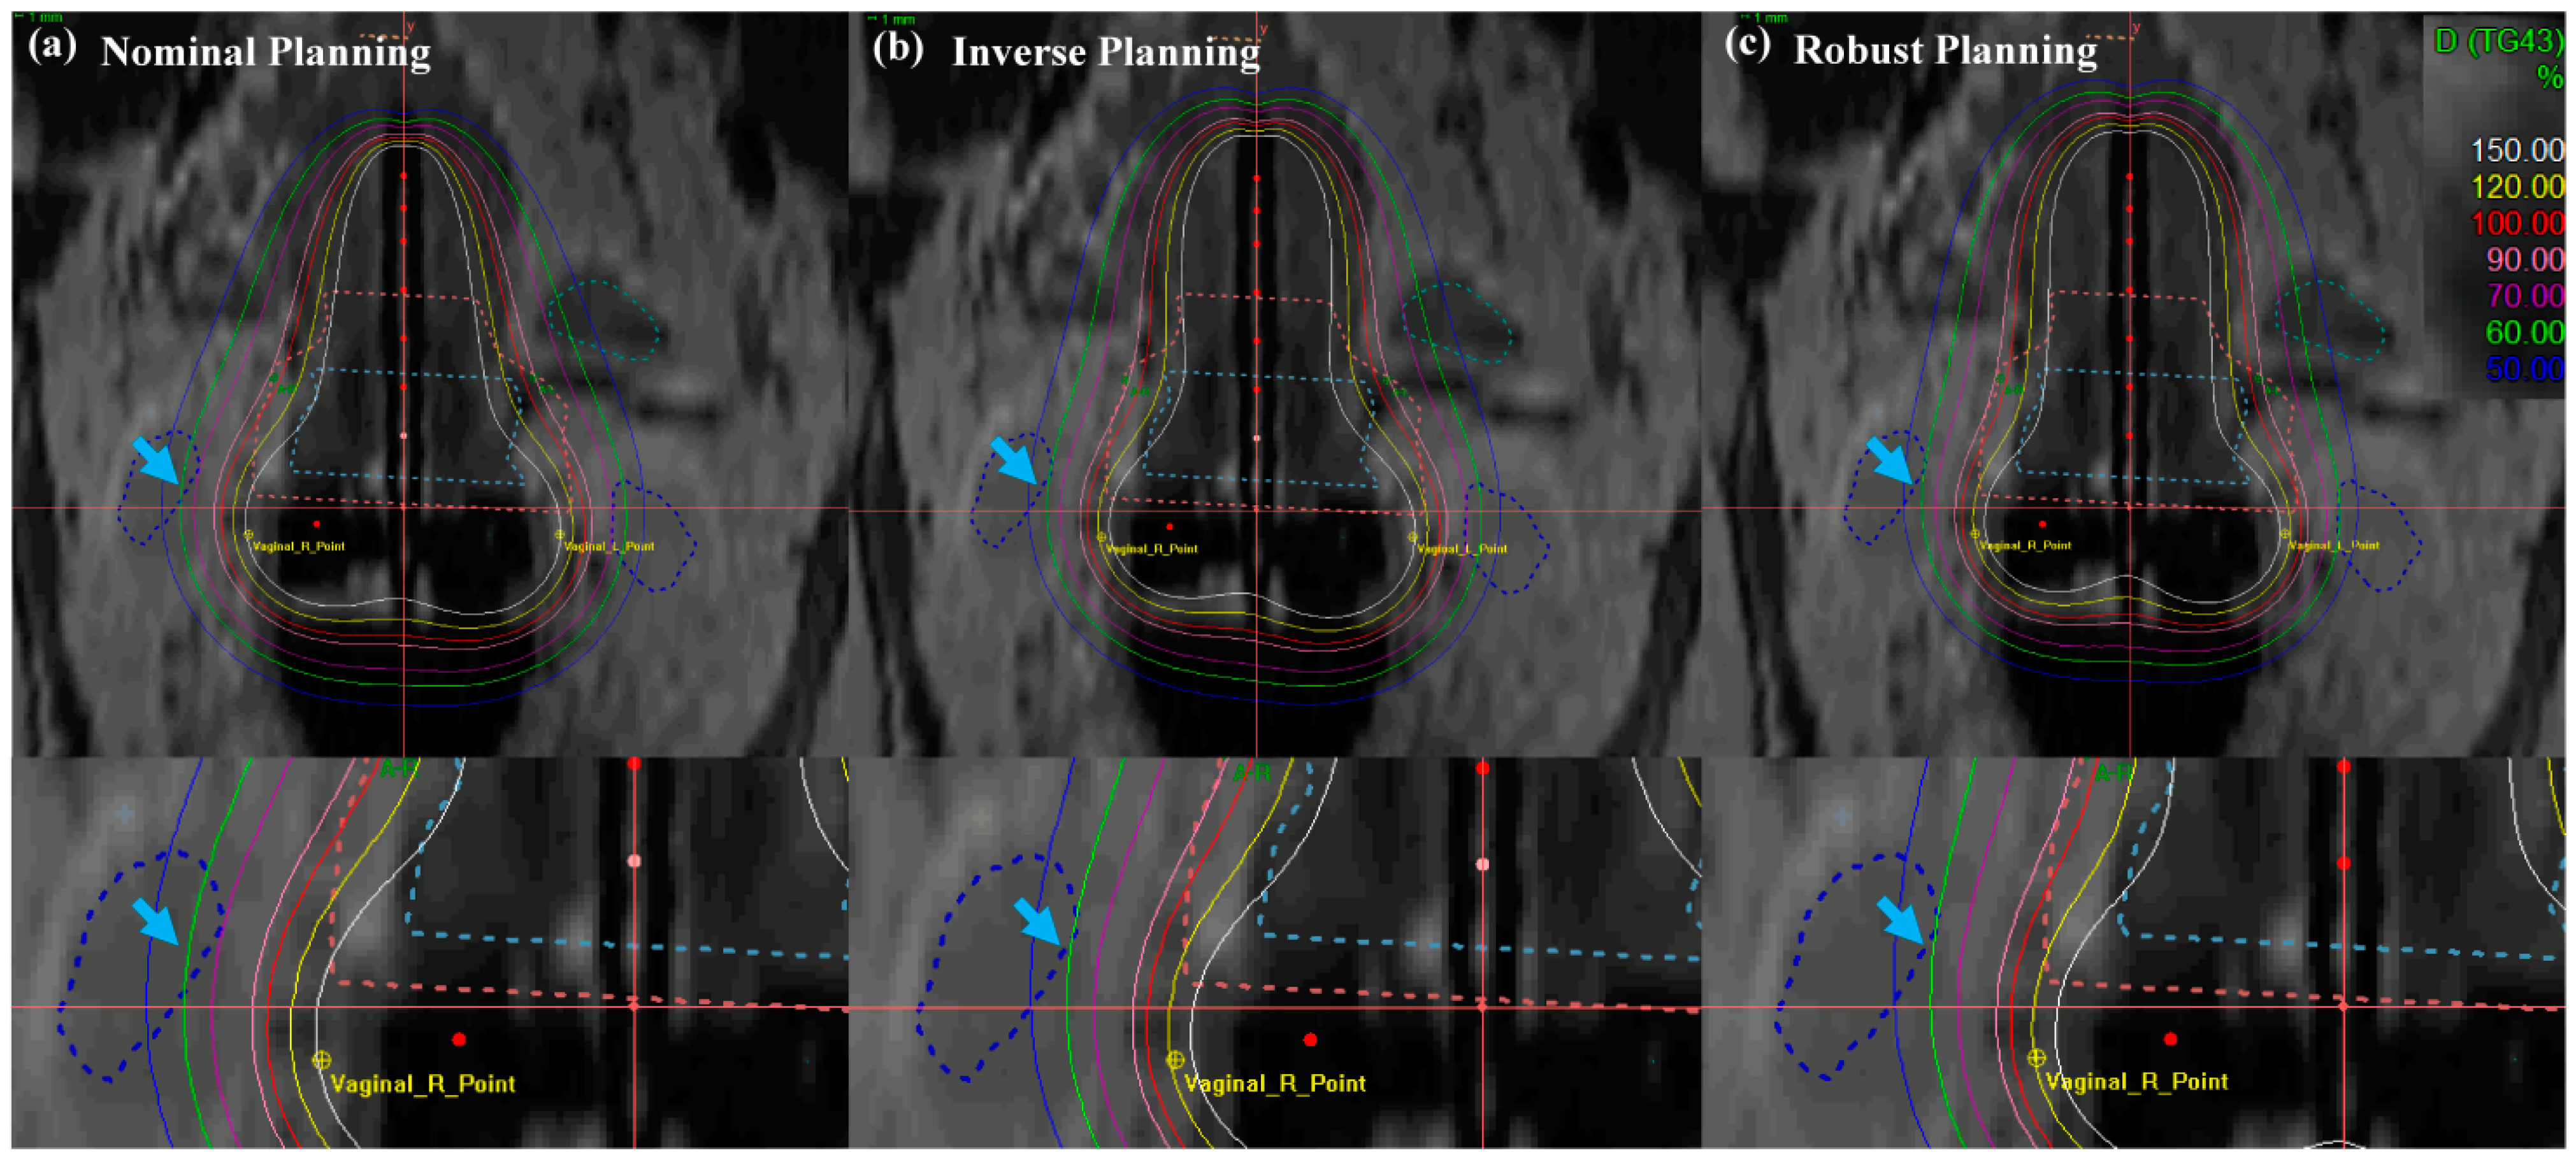

3.2.2. Isodose Lines